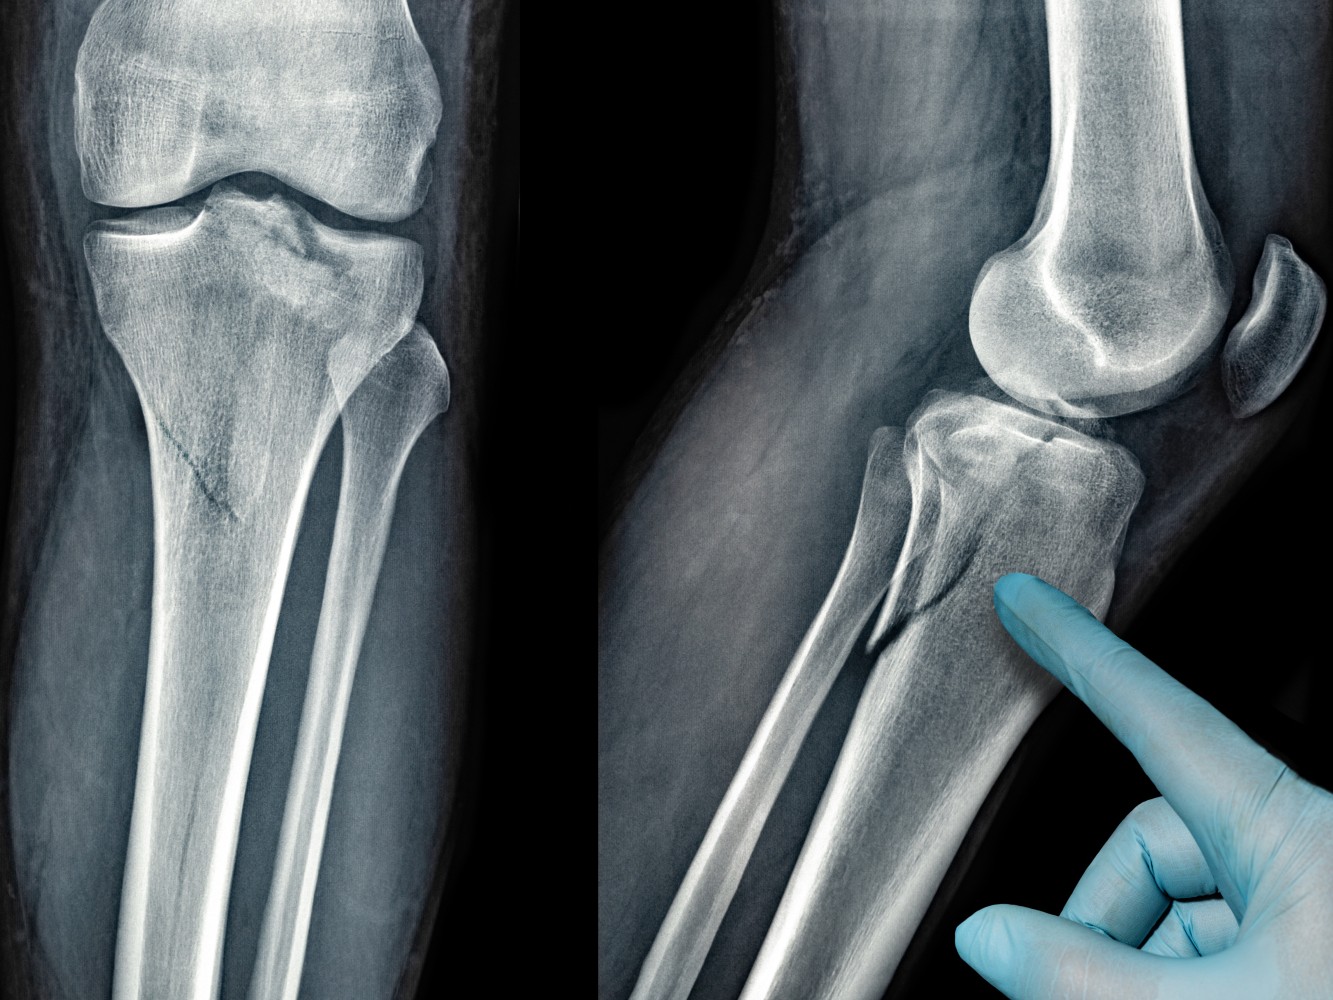

He has completed MBBS, MS [ORTHOPAEDICS], DNB [ORTHOPAEDICS], FIJR, FIAS, FIAT followed by specialized fellowships in Advanced Trauma, Robotic & Conventional Joint Replacement, and Arthroscopy. His clinical expertise spans adult and pediatric trauma, fracture management, joint replacement surgeries, sports injuries, and spine-related conditions.

Dr. Anmol has treated 2000+ patients and has been involved in 500+ orthopaedic surgeries, including complex trauma cases and advanced joint replacement procedures. His exposure to robotic joint replacement and arthroscopy allows him to offer precise, minimally invasive solutions with faster recovery and improved outcomes.